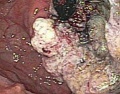

贲门癌